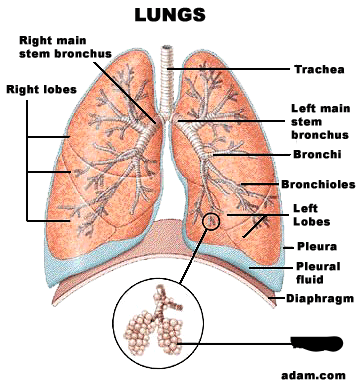

Alveolus/alveoli

Bronchioles

C-Rings (=tracheal cartilage)

Horizontal fissure (of right lung)

Left/right oblique fissue (of lung)

Left/right primary bronchus/bronchi

Pulmonary capillaries

Secondary bronchi

Upper/middle/lower lobe (of lung)